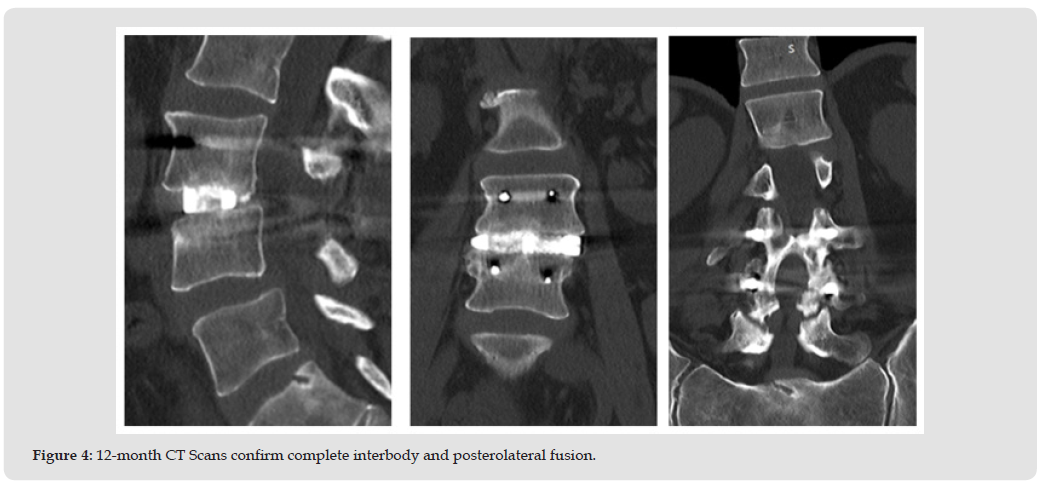

At the 3-month follow-up radiographs showed the instrumentation intact and in good position (Figure 2). Clinically the patients’ pain symptoms had improved dramatically (VAS Back-1.4/10, VAS Right Leg-0.4/10, VAS Left Leg-0.9/10, ODI -50%) and the patient continued physical therapy. CT scans were obtained at the next follow- up (8.2 months) due to a moderate increase in pain symptoms (VAS Back-6.0/10, VAS Right Leg-7.6/10, VAS Left Leg-1.0/10, ODI- 34%) as a result of increased activity and reduction of pain medication however the ODI had improved to moderate disability. The CT scans exhibited early and complete interbody and posterolateral fusion success (Figure 3). By the 1-year follow-up the symptoms had mostly resolved with minor residual back pain and complete resolution of radicular pain (VAS Back-2.0/10, VAS Right Leg-0/10, VAS Left Leg-0/10, ODI-26%) with a clinically significant improvement of 22 points from pre-op in the ODI. CT Scans taken at 1 year confirm complete fusion in both the interbody and posterolateral constructs seen previously (Figure 4).

The bone graft used for this case (Catalyst) was selected based on its handling and performance characteristics in a wide range of patients, most of which had multiple risk factors for failure. [11-13] Of particular interest with this case was fusion success in both the interbody and posterolateral constructs at 8 months in an active smoker, demonstrating rapid bone formation consistent with the dual pathways of both endochondral and intramembranous ossification. [9,10] This supports the versatility of Catalyst Bone Graft as an effective bone graft substitute in challenging patients. The combination of surgeon skill and experience in selecting the most appropriate and effective surgical procedures and adjuncts, including the choice of bone graft, resulted in a positive clinical outcome in this patient.